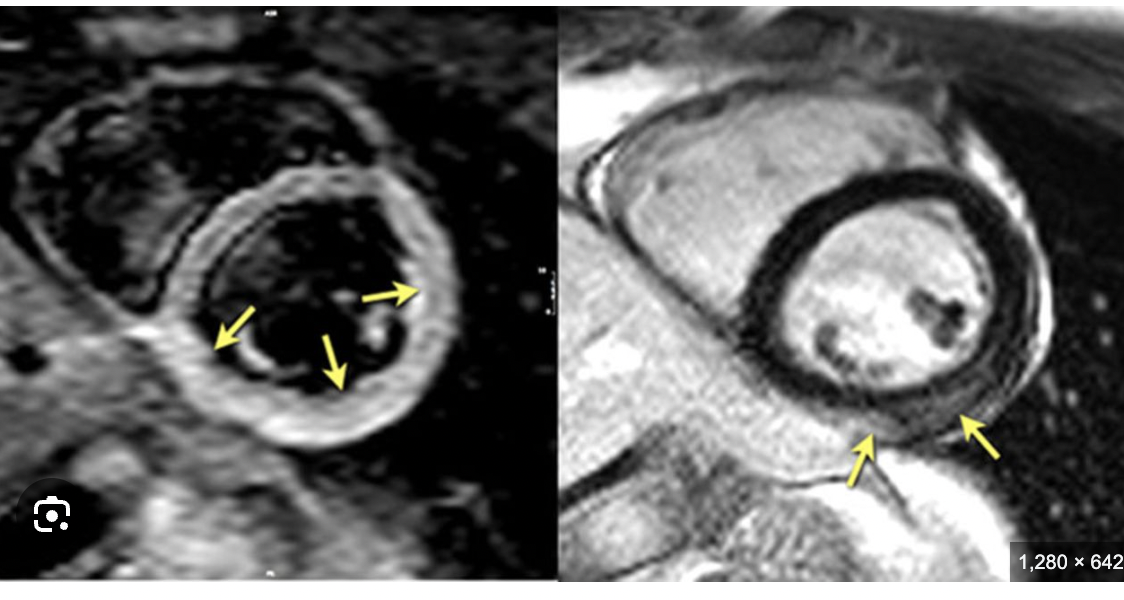

Cardiac MRI

• Show inflammation